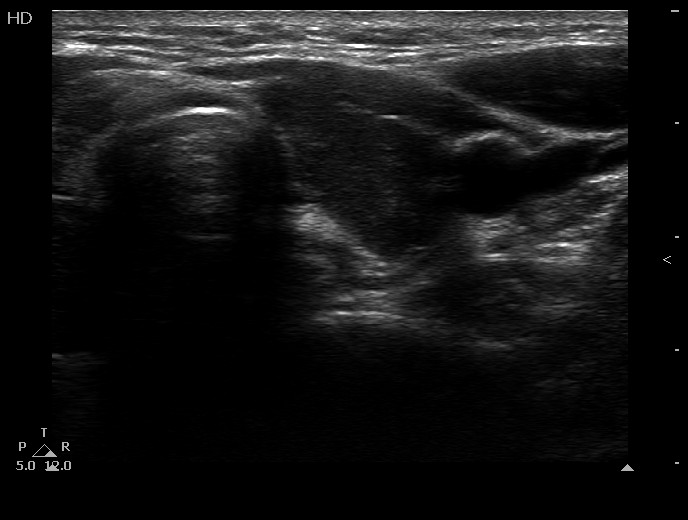

100 consecutive cases of papillary cancer - case 054 (ultrasonographic picture 7)

Left lobe, transverse scan. This lobe is also hypoechogenic.